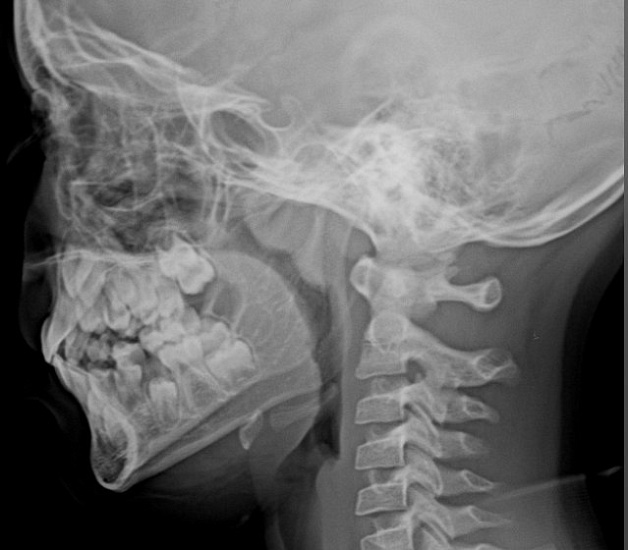

Рентгенография носоглотки – важный метод прицельного исследования, который позволяет оценить состояние носоглотки и ее просвет.

Диагностическая услуга выполняется в одной проекции.

Как проводится рентген носоглотки?

Сканирование выполняется в течение 10 минут, что позволяет быстро получить необходимую информацию.

Результаты исследования обычно готовы в течение дня, но при острой патологии они могут быть предоставлены сразу.